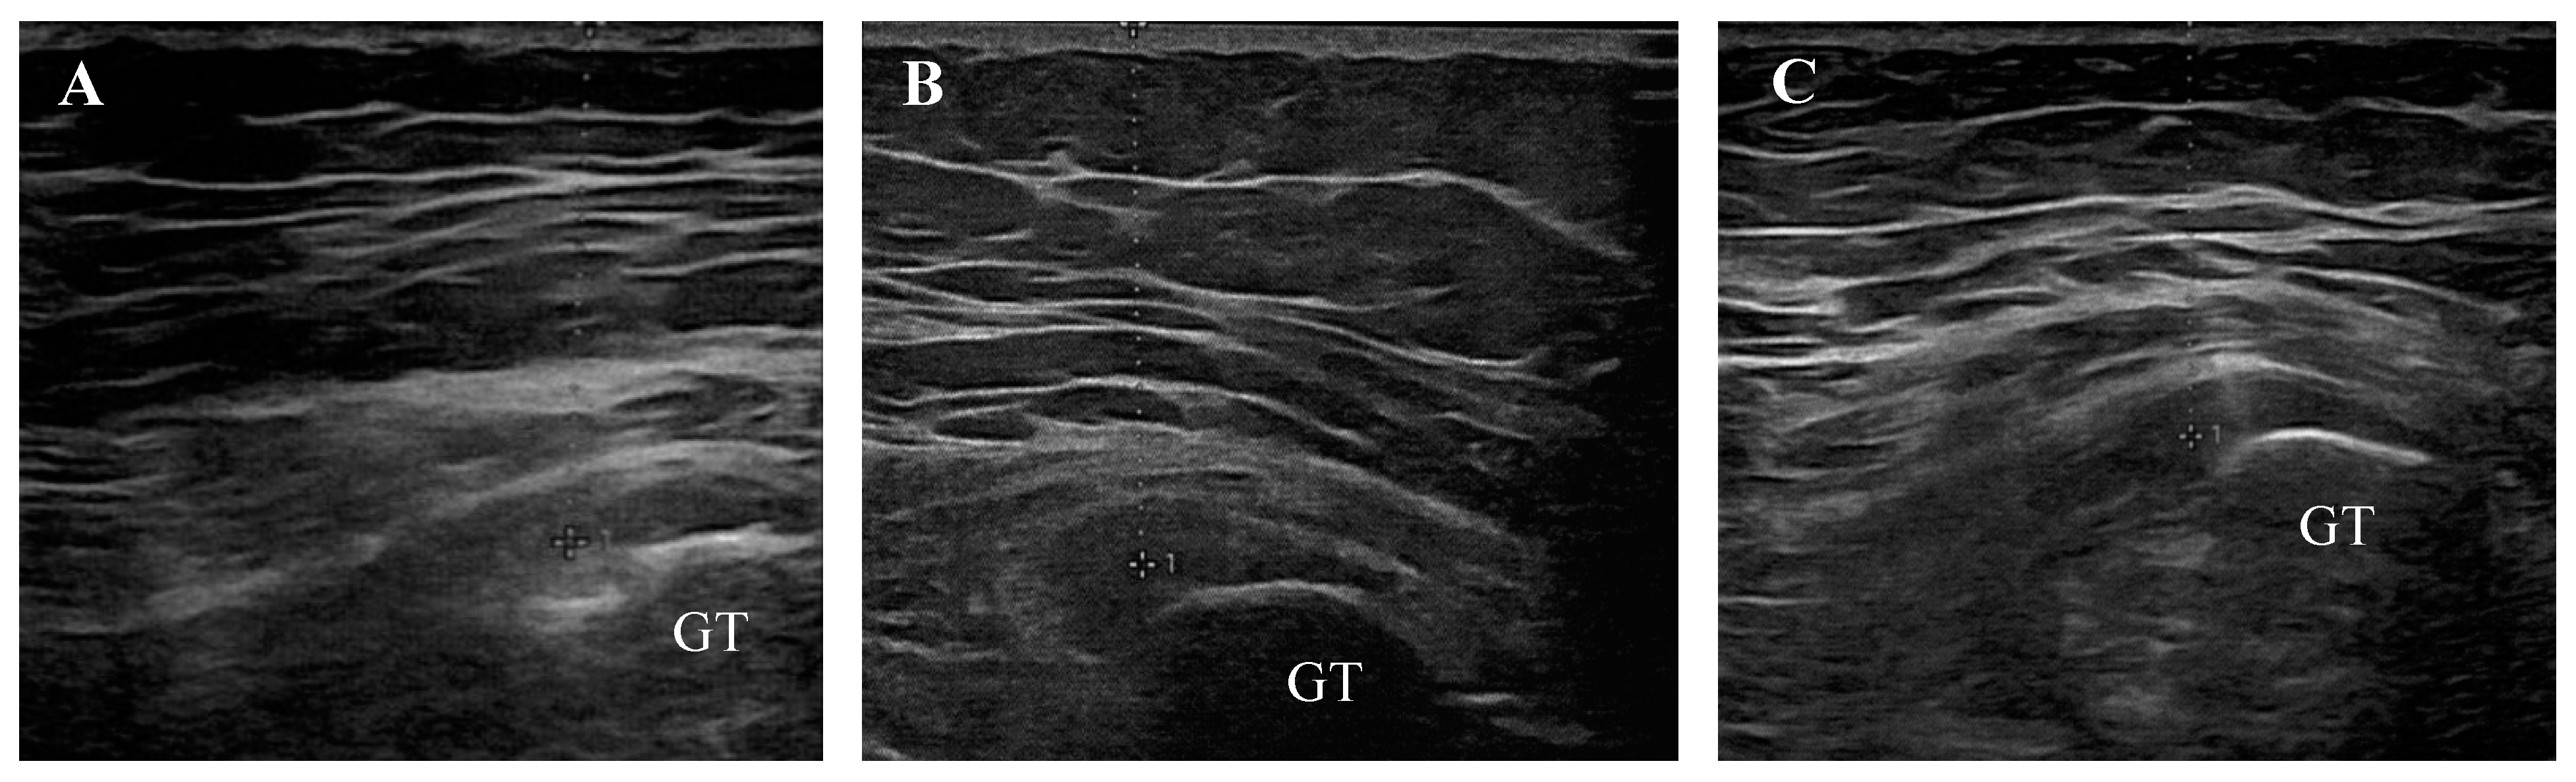

- Manske, R.C.; Wolfe, C.; Page, P.; Voight, M.L.; Bardowski, E. The Utilization of Diagnostic Musculoskeletal Ultrasound in the Evaluation of Gluteus Medius Tendon Pathology: A Perspective for Rehabilitation Providers. Int. J. Sports Phys. Ther. 2024, 19, 642–645. [Google Scholar] [CrossRef] [PubMed]

- Saad, A.; McLoughlin, E.; S Kalia, S.; Almeer, G.; C Azzopardi, C.; Botchu, R. Gluteus Medius Muscle Pathologies—A Case Series & Pictorial Review. J. Orthop. 2020, 21, 270–274. [Google Scholar] [CrossRef] [PubMed]